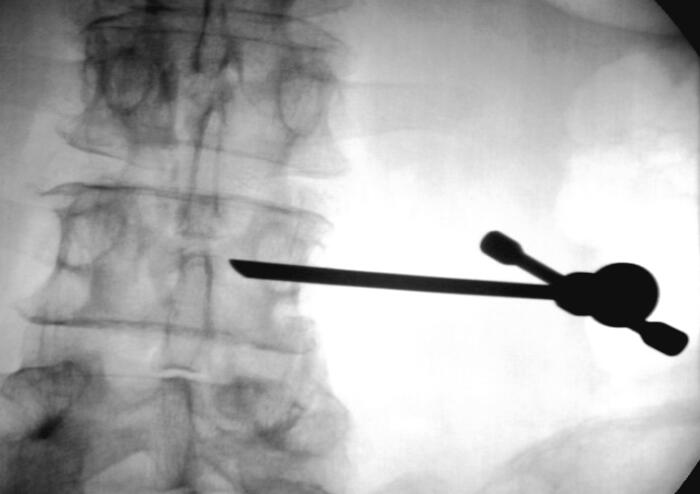

4、單側(cè)穿刺入路